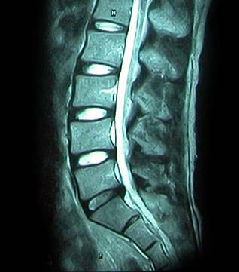

• 척추 방사선 사진1